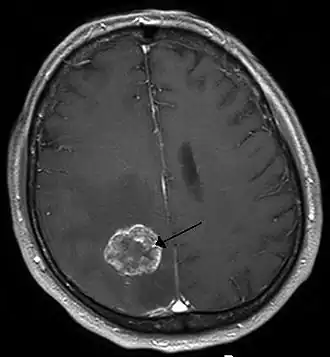

Afbeelding van een MRI-scan van een uitzaaiing van longkanker in de rechterhersenhelft (L=links, P=occipitaal, achterkant van het hoofd).